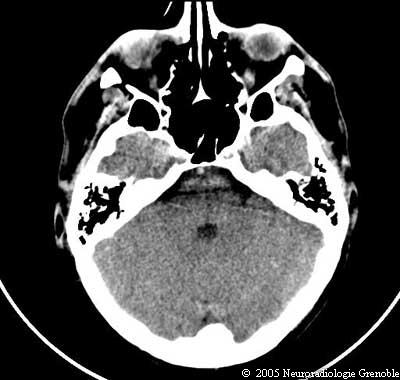

Radioanatomie TDM de l'encéphale

TDM cérébrale sans injection